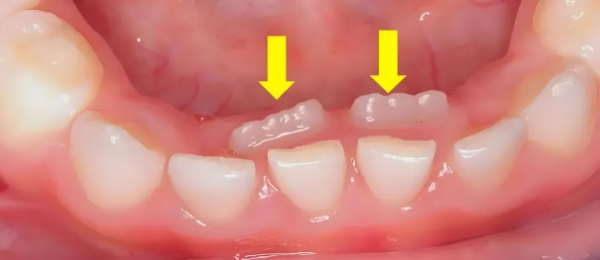

正常情况下,孩子的乳牙会在6-12岁期间逐渐脱落,为恒牙让出位置。当乳牙尚未脱落,而恒牙已经从牙龈内侧或外侧萌出时,就形成了“双排牙”。

这种现象最常见于下前牙区域,其次是上前牙区域。数据显示,近年来儿童双排牙的发病率显著上升,已成为儿童口腔科的常见问题。